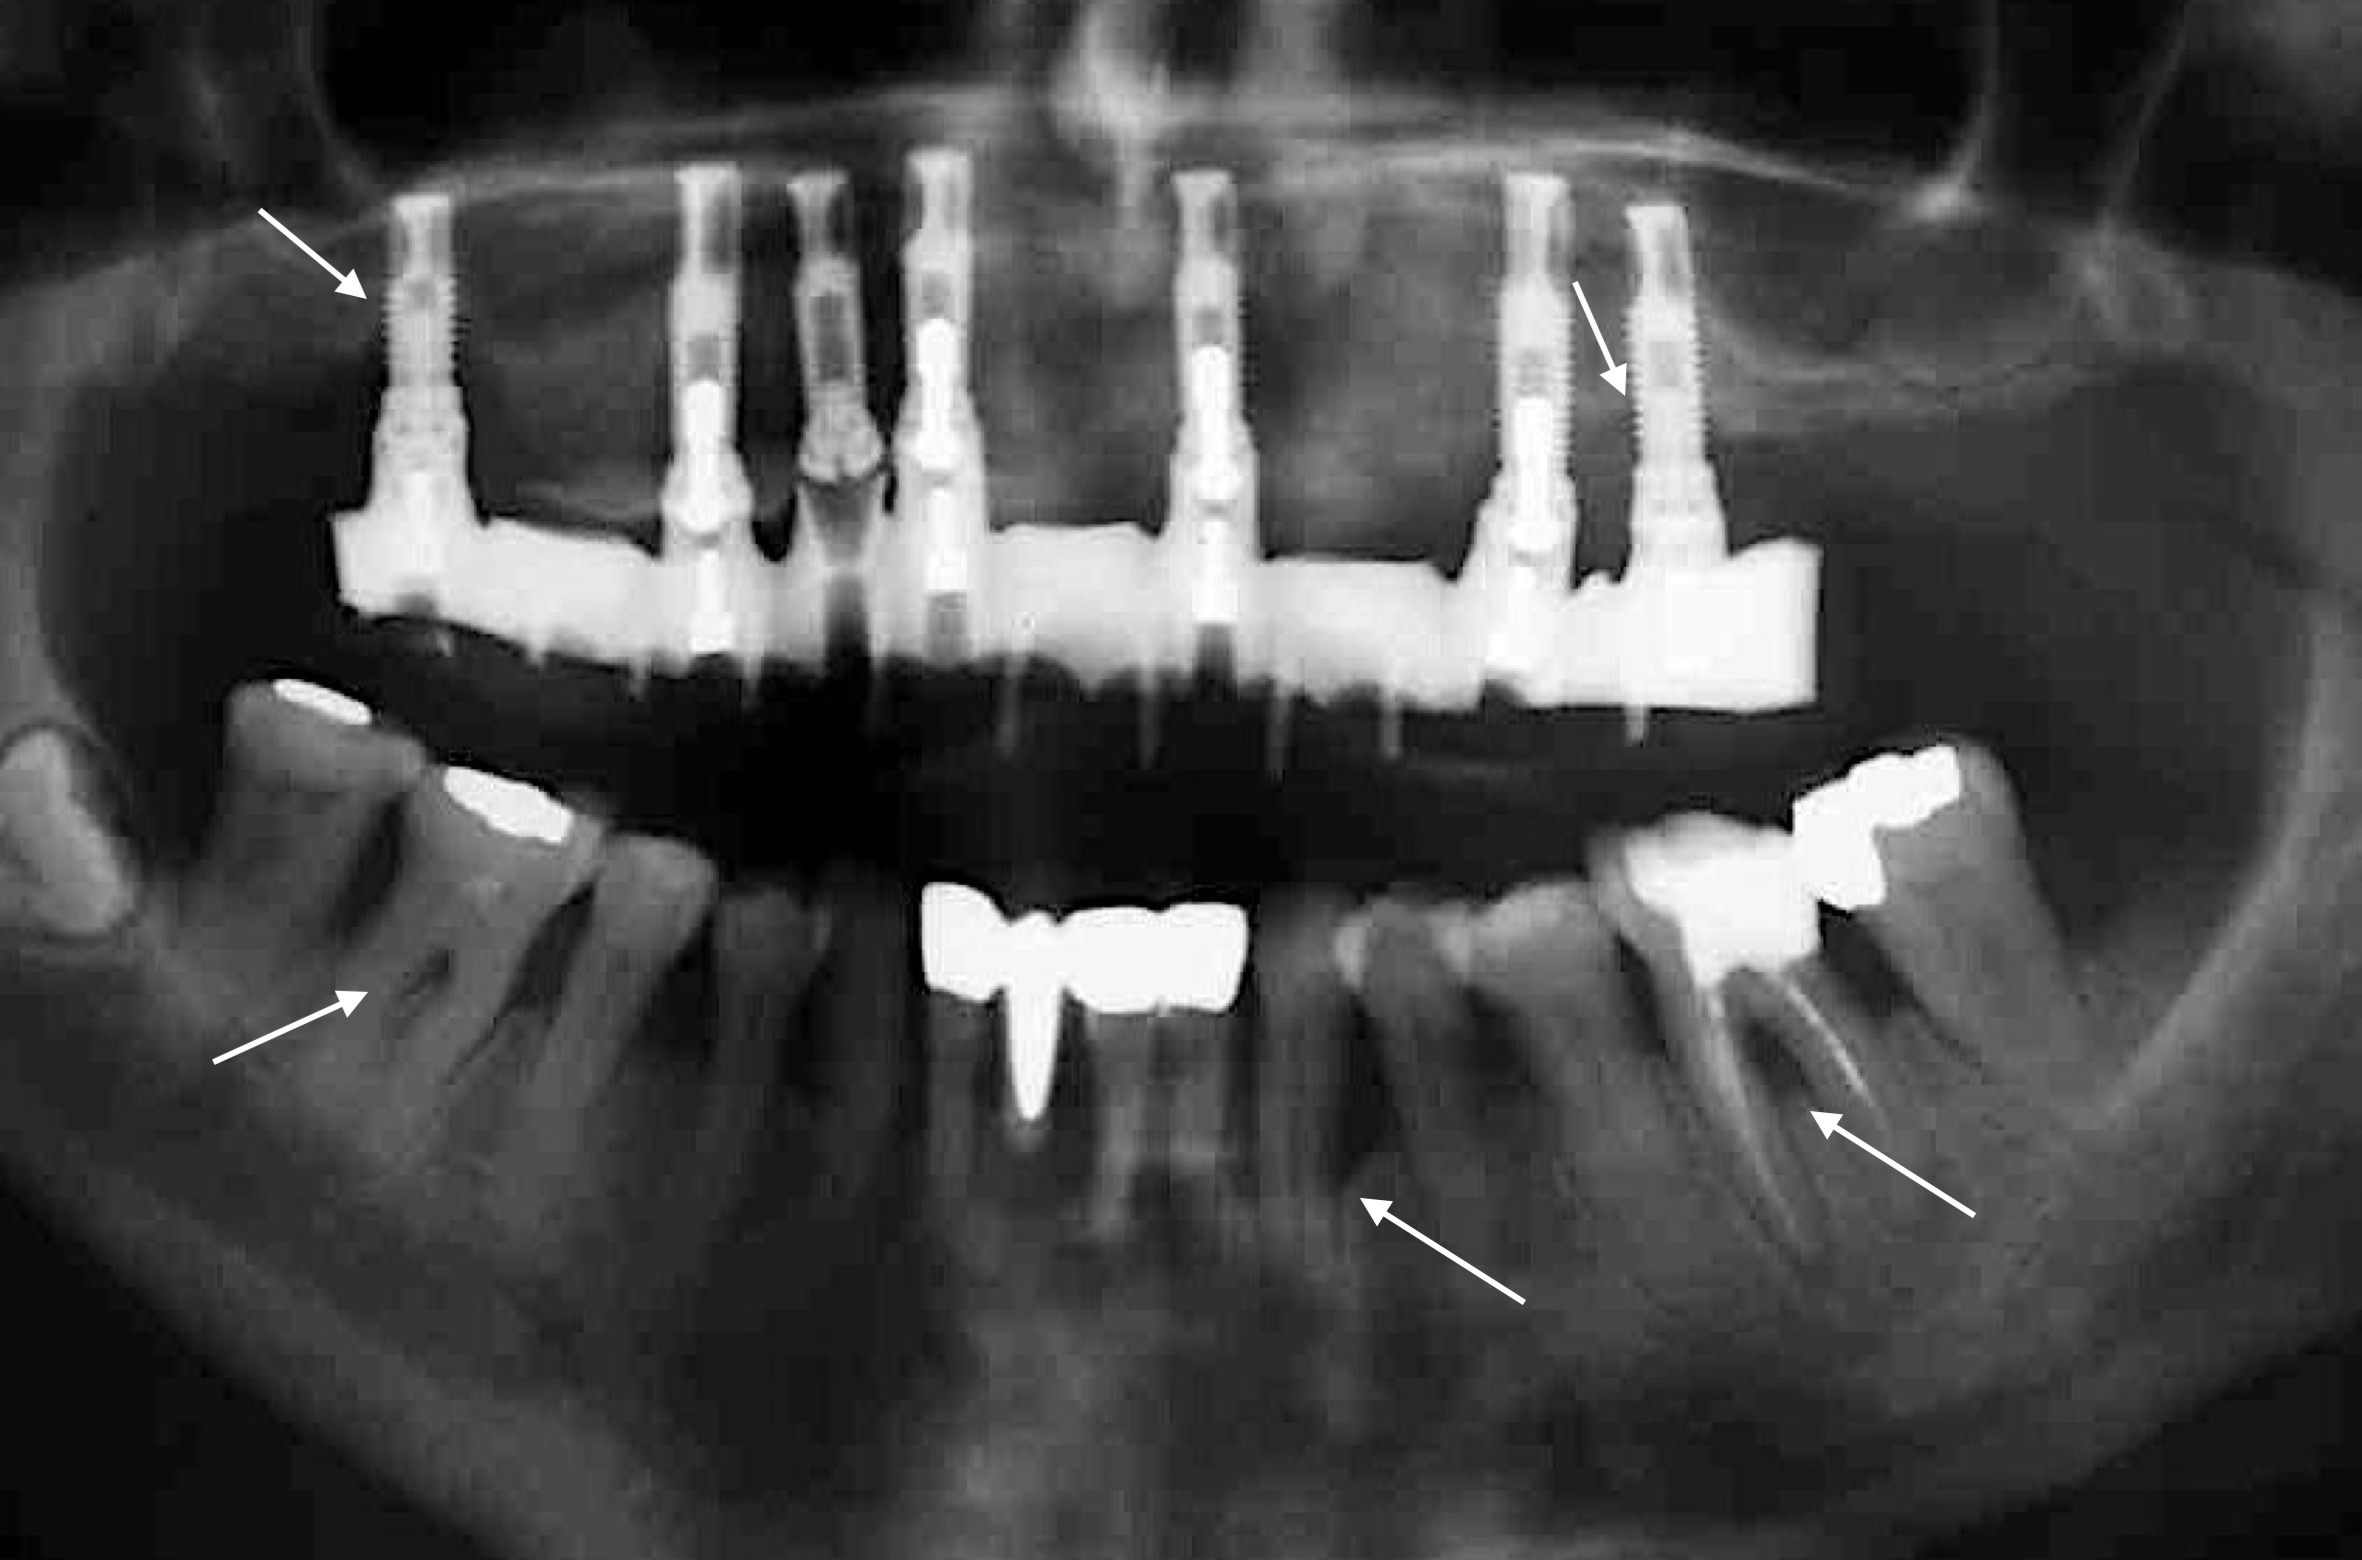

Zahlreiche Übersichtsarbeiten der letzten 10 Jahre belegen ein höheres Risiko eines Implantatmisserfolgs bei PatientInnen mit parodontaler Grunderkrankung (z.B.: Renvert & Persson 2009, Sousa et al. 2016, uvm.) und dieses Risiko scheint bei PatientInnen mit der Diagnose „generalisierte aggressive Parodontitis“ noch zusätzlich erhöht zu sein (Monje et al. 2016). Um diese Komplikation möglichst zu vermeiden, gilt es den/die Patienten/Patientin parodontal möglichst gut im Griff zu halten! Das bedeutet: 1) Die parodontale Therapie muss vor der Implantattherapie stattfinden; 2) Strikte Optimierung der Mundhygiene und vor allem gezielte Re-instruktion nach Eingliederung der Implantat-getragenen Versorgung; 3) Planung und Durchführung regelmäßiger Recallsitzungen um einerseits kein Rezidiv in Bezug auf die Parodontitis zu erleiden und andererseits peri-implantäre Erkrankungen frühzeitig zu erkennen; und 4) Rest-Sondierungstiefen nach der parodontalen Therapie möglichst vermeiden! Warum ist letzteres so wichtig? Eine Studie aus Australien (Cho-Yan Lee et al. 2012) hat sehr schön gezeigt, dass das Risiko eine Peri-implantitis zu entwickeln bei Parodontitis-PatientInnen mit Restsondierungstiefen (≥ 6mm Sondierungstiefe) im Vergleich zu Parodontitis-PatientInnen ohne Restsondierungstiefen und parodontal gesunden PatientInnen 4- bis 5-fach erhöht ist!